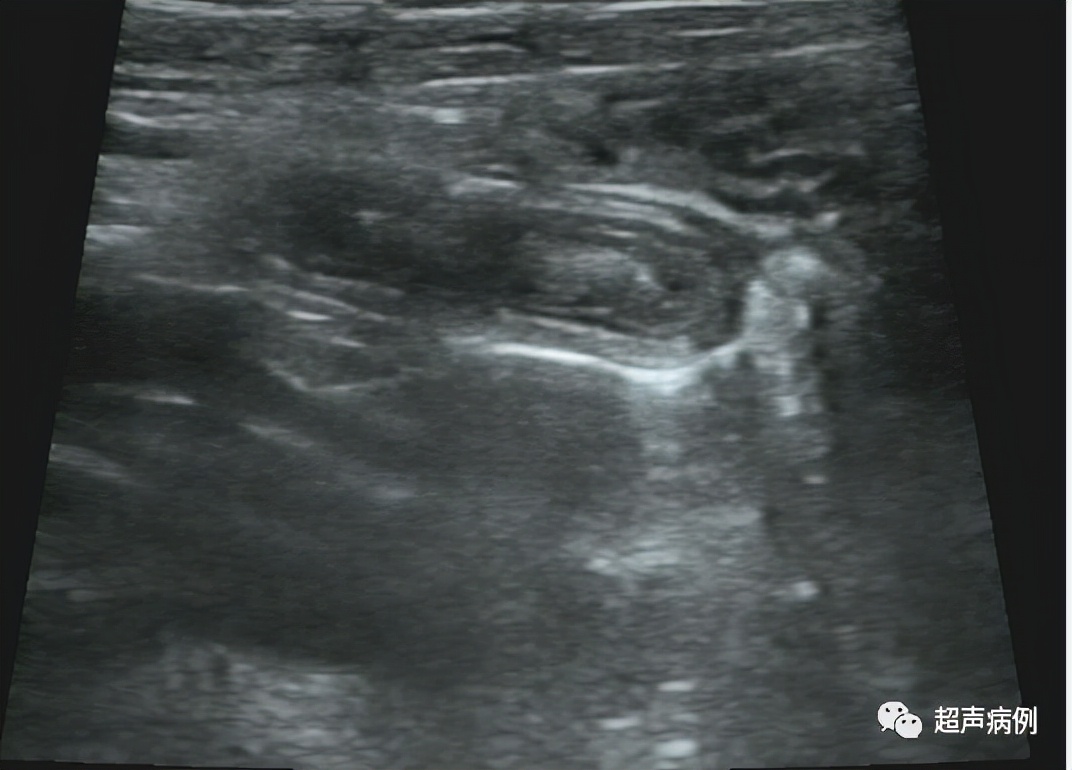

病例4

男,43岁。转移性右下腹痛2天

超声检查:

右下腹阑尾解剖区查见一范围约3.7x1.2cm管状弱回声,其内可见团状强回声,周边组织回声增强。CDFI:未见明显血流信号。

病理诊断:急性坏疽性阑尾炎及其周围炎。